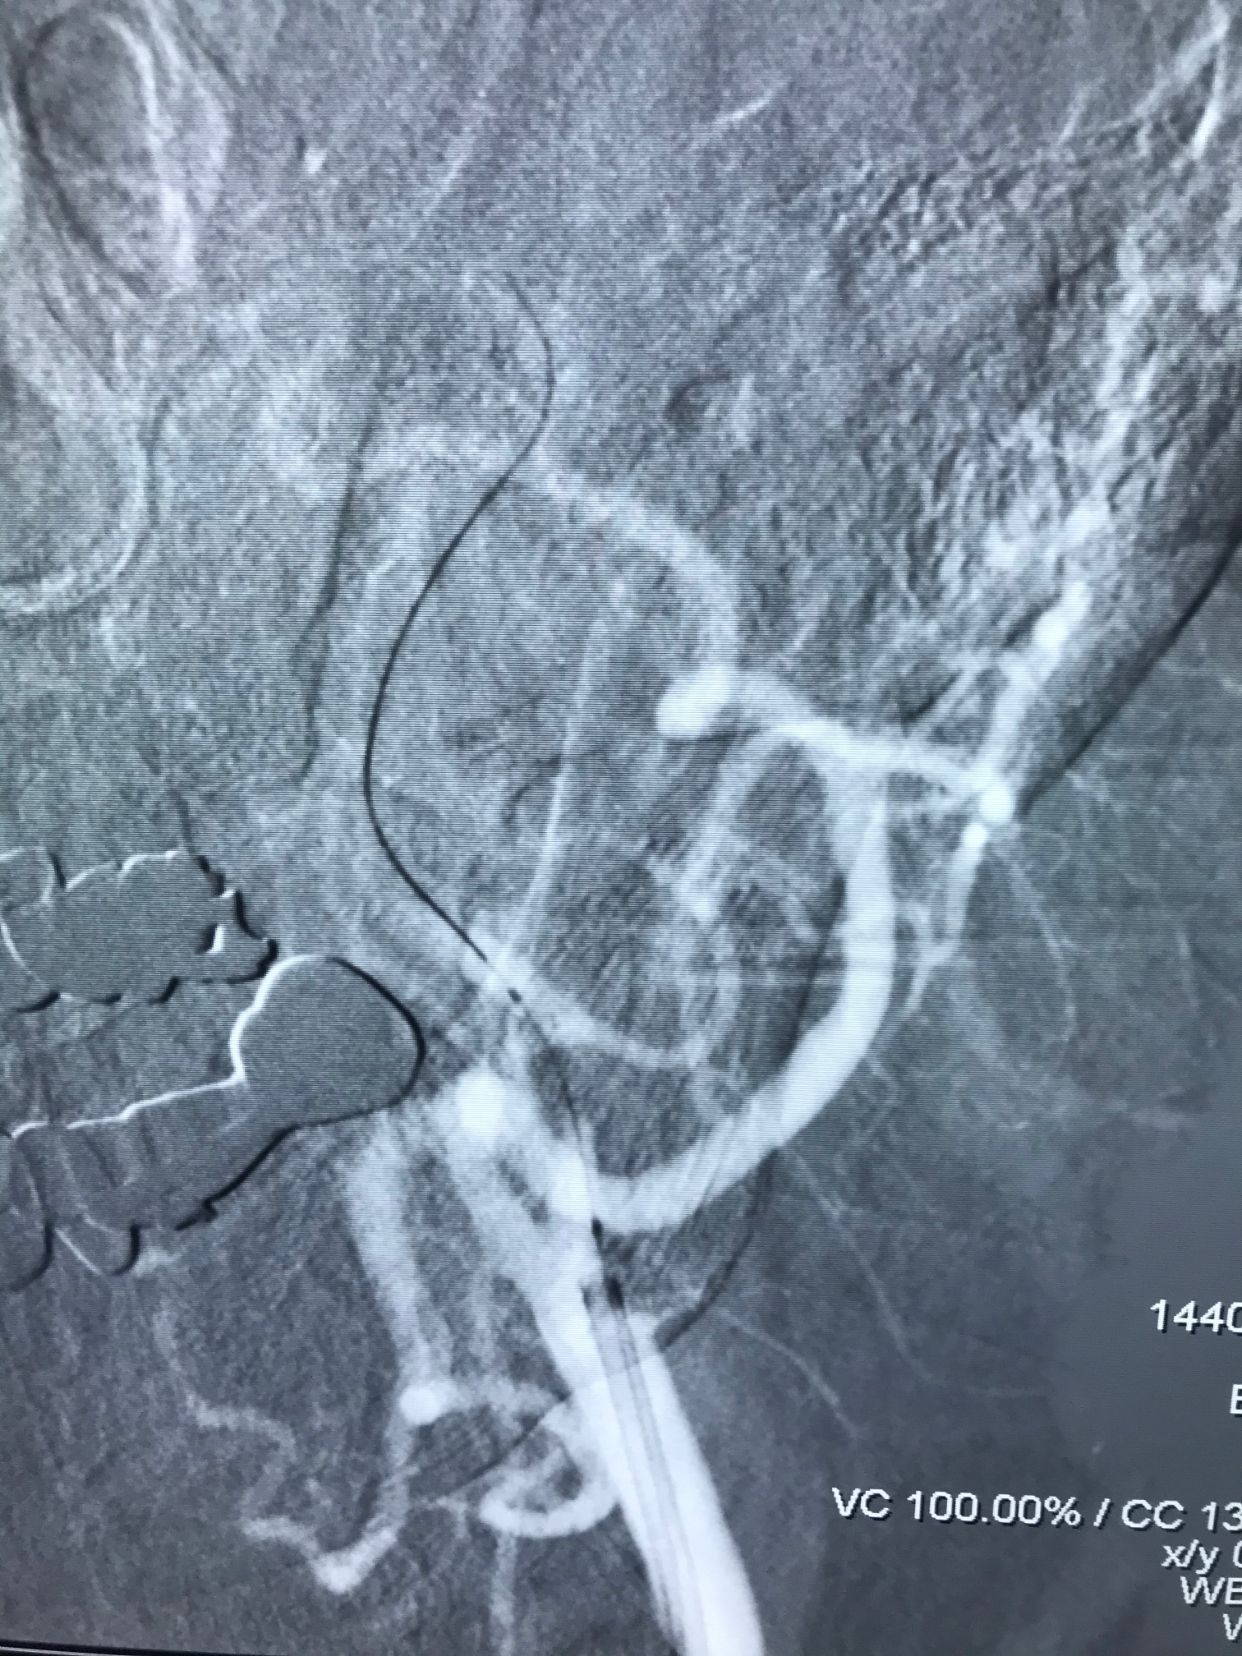

保护伞下球囊扩张支架植入!

血流恢复!